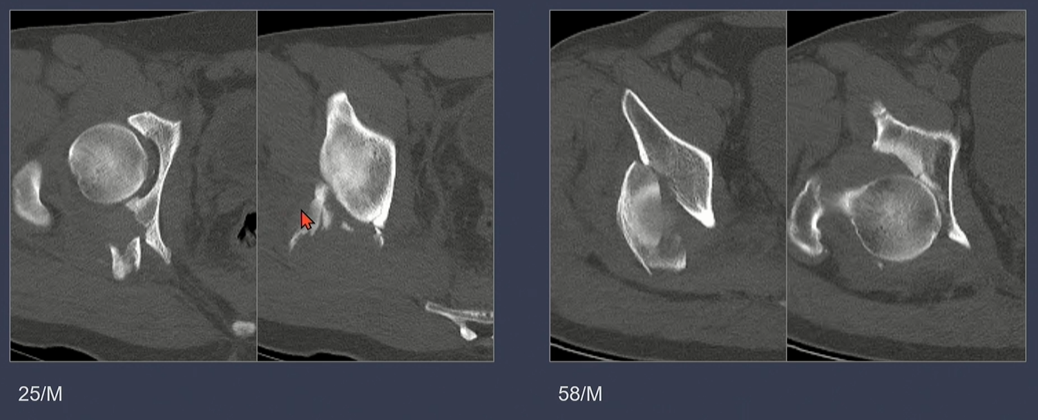

노란색 화살표: anterior column + 녹색 화살표 posterior hemitransverse

iliac wing쪽 골절선(녹색 점선)에 더해서, sciatic notch로 이어지는 골절선(녹색 화살표)을 확인.

노란색 별은 buttress 부위.